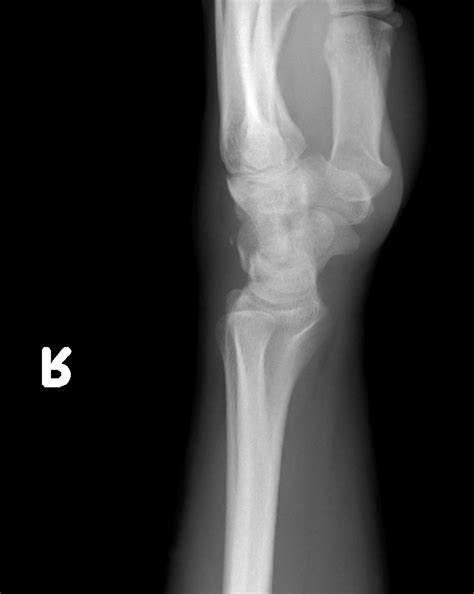

• X-rays: Standard X-rays can often reveal a fracture in the triquetral bone. However, due to the small size of the bone, additional views or specialized imaging may be required.

• CT scan: A computed tomography (CT) scan provides detailed images of the bone and can help identify fractures that are not visible on standard X-rays.